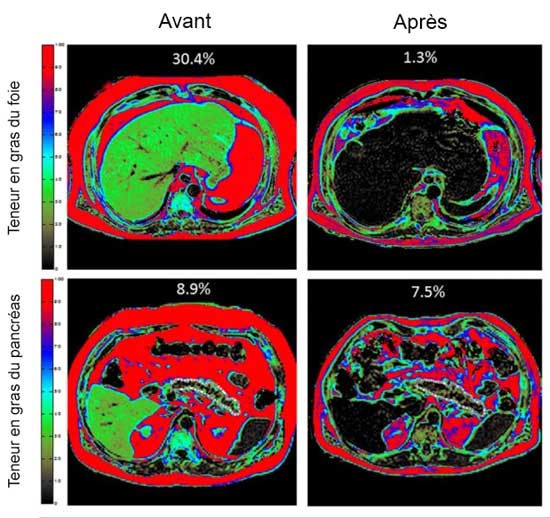

Pour y parvenir, les volontaires ont évidemment dû suivre une diète faible en calories tout en réapprenant à mieux manger et à diminuer naturellement la glycémie. Très vite, la teneur en gras de leur foie et celle de leur pancréas (deux signes révélateurs du diabète) ont diminué, mais il a fallu attendre plusieurs mois pour que les cellules béta-pancréatiques retrouvent leur état de forme initiale et pour que la sensibilité à l’insuline redevienne significative.

Roy Taylor, Ahmad Al-Mrabeh, Sviatlana Zhyzhneuskaya, Carl Peters, Alison C. Barnes, Benjamin S. Aribisala, Kieren G. Hollingsworth, John C. Mathers, Naveed Sattar, Michael E.J. Lean. Remission of Human Type 2 Diabetes Requires Decrease in Liver and Pancreas Fat Content but Is Dependent upon Capacity for β Cell Recovery. Cell Metabolism, 2018; DOI: 10.1016/j.cmet.2018.07.003